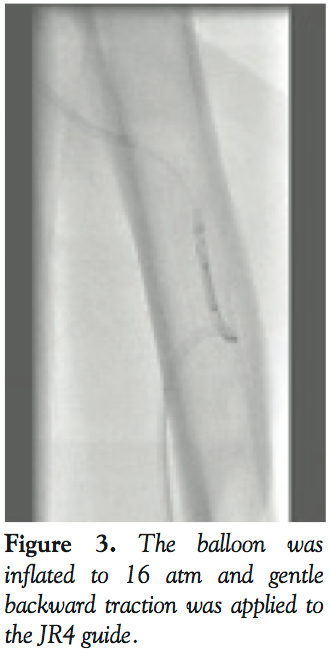

We elected to convert to a right femoral approach with a view to rescue the kinked catheter with use of a vascular snare. However, due to a lack of an available appropriately-sized snare and concerns with the use of a large-caliber sheath in an octogenarian with peripheral vascular disease, we explored other options. We elected to use a novel balloon retrieval technique. A 6 Fr JR4 guide was used to enter the left subclavian artery and manipulated to lie within close proximity of the kinked EBU 3.5 catheter. A Whisper MS wire was advanced through the JR4 guide in an attempt to enter the distal end of the kinked guide catheter (Figure 2). Eventually, the Whisper wire passed into the kinked catheter and was manipulated into the proximal limb of the kinked guide. A 3.0 x 15 mm NC balloon was then passed through the JR4 guide over the guidewire into the distal end of the kinked guiding catheter. The balloon was inflated to 16 atm and gentle backward traction was applied to the JR4 guide (Figure 3). Eventually, both the JR4 guide and the kinked catheter were brought back to the ascending aorta (Figure 4). The catheter was untwisted using the JR4/balloon system that enabled controlled manipulation in the ascending aorta, enabling the EBU 3.5 guide to be removed from the left radial sheath with the use of a standard 0.035˝ wire. Following the procedure, the patient had a good radial pulse without complication.